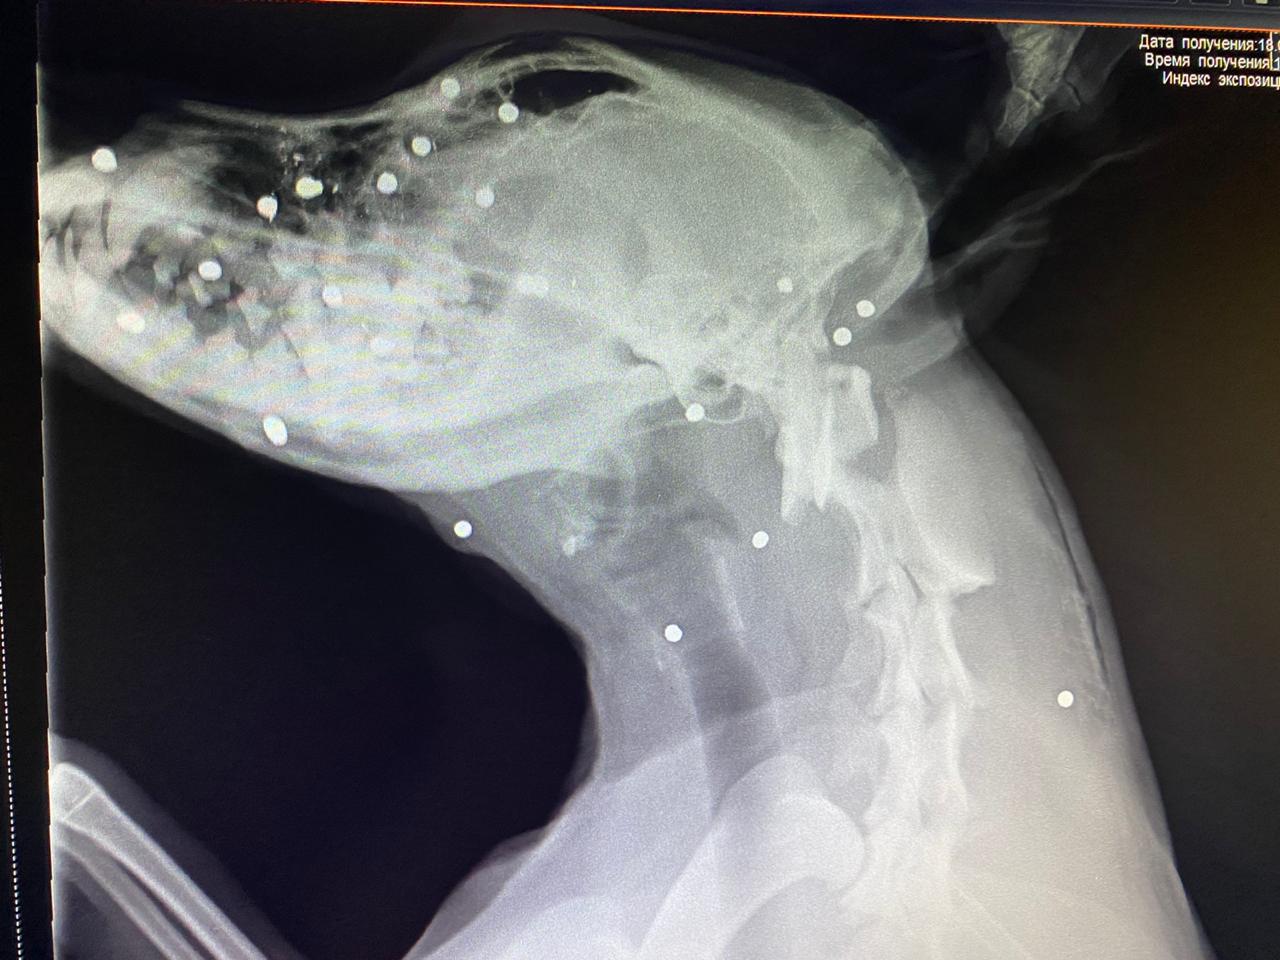

Пострадала Лелька, годовалая сучка. Марина бросила все и повезла ее в ветклинику. Из собаки достали 20 металлических осколков. Московские волонтеры предложили помощь, и собаку отправили рейсом в столицу. Сейчас ее состояние – стабильное, средней тяжести, по словам врачей, угрозы жизни нет. Тем не менее, существует вероятность, что собака лишится зрения.